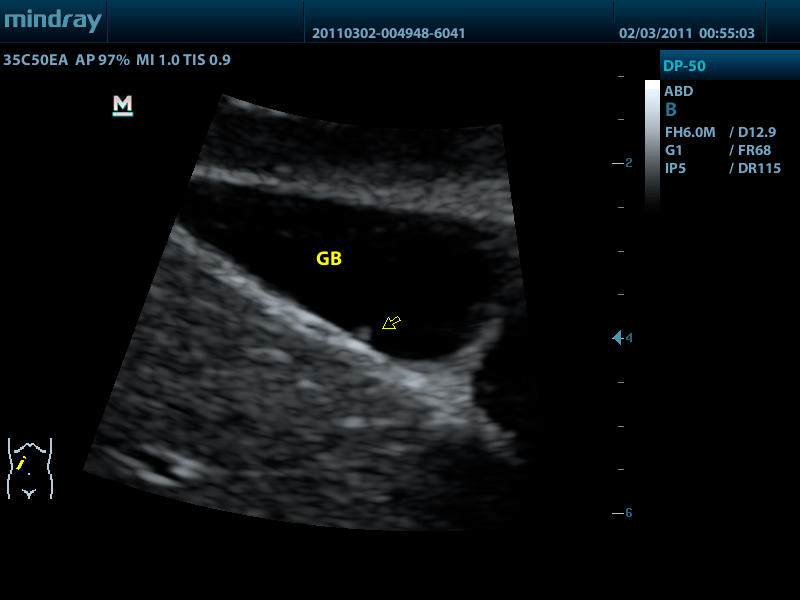

Портативный ультразвуковой сканер Mindray DP-50

Mindray DP-50 – портативная цифровая ультразвуковая система с ЖК монитором 15 дюймов (1024Х768)

Достоинства Mindray DP-50:

- iClear технология подавления помех и получения четких ультразвуковых изображений высокого разрешения

Качество изображения:

- iBeam: функция улучшения разрешающей способности изображения

- iClear: функция подавления шумов на изображении для улучшения детализации и контрастности изображения

- iTouch: функция оптимизации изображения нажатием одной клавиши

- iZoom: увеличение рассматриваемого участка изображения на весь экран

Применяемые датчики DP-50:

Конвексный датчик 35C50EA (2.0/3.5/4.5/5.0/Н5.0/Н6.0) R50